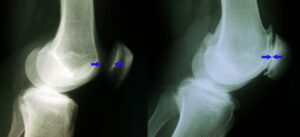

(Left) This X-ray shows a normal knee from the side. The arrows point to the normal amount of space between the bones.

(Right) This X-ray shows narrowed joint space and bone rubbing on bone due to arthritis.